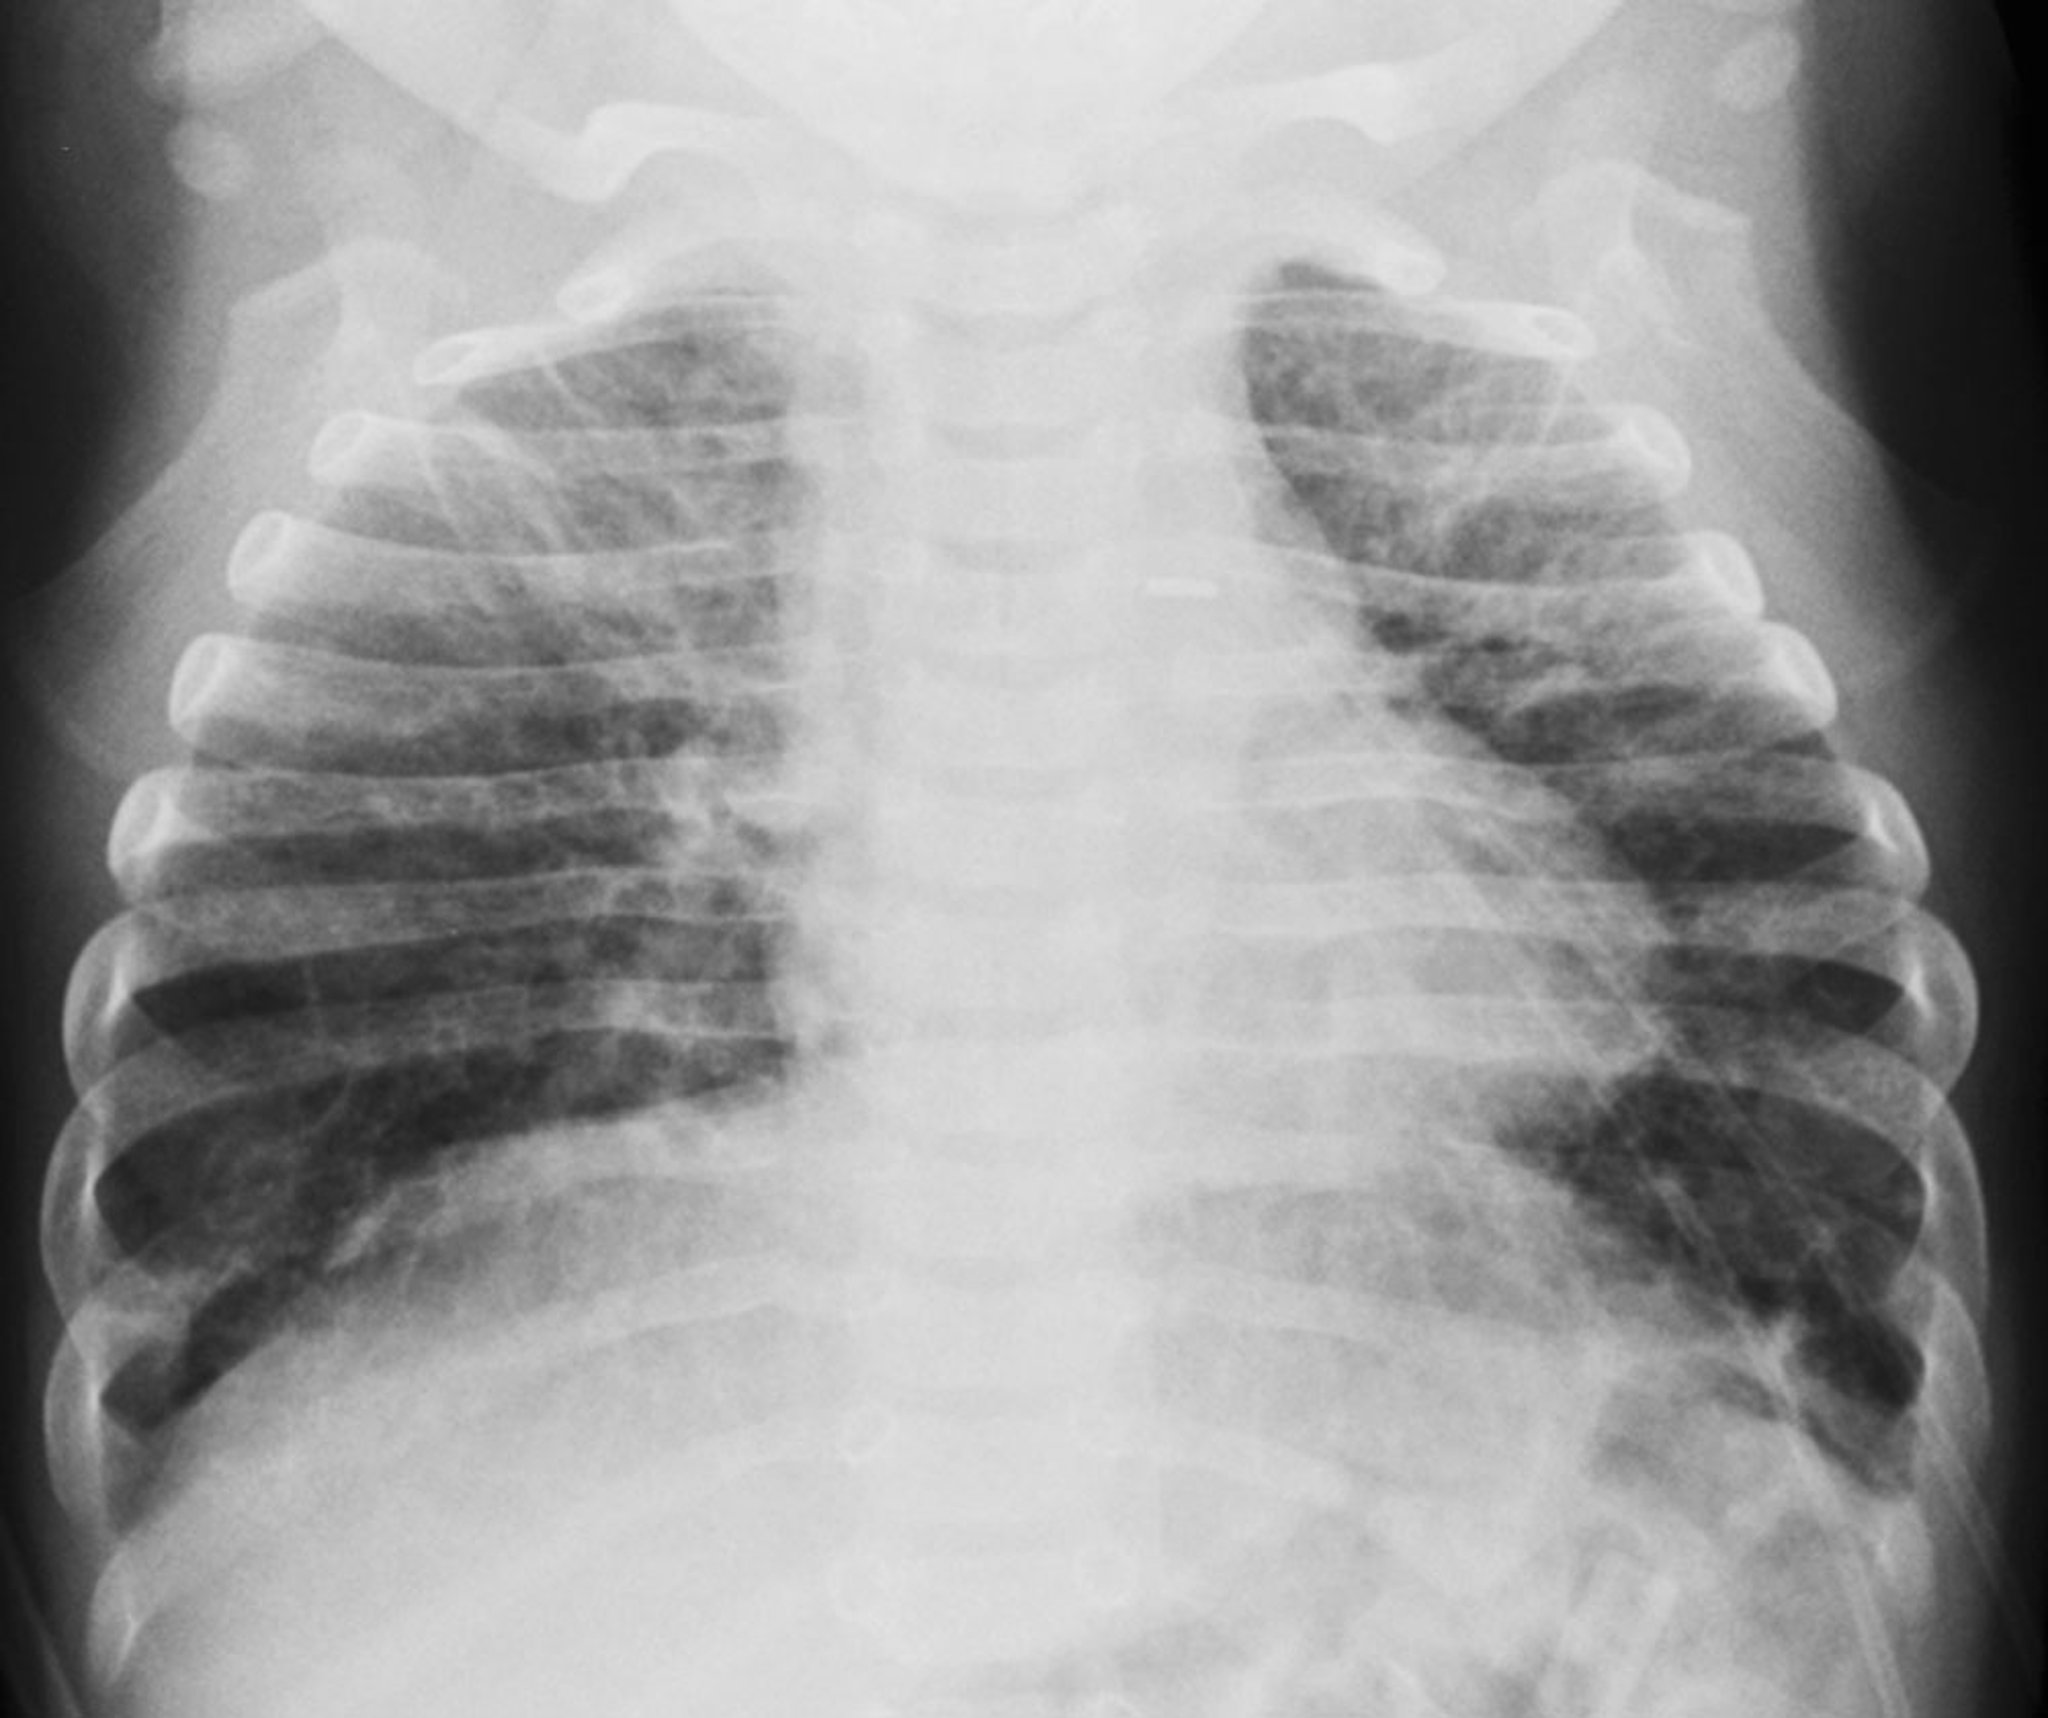

支气管肺发育不良(X 射线和 CT 结果)

这些图像中的婴儿有早产史和支气管肺发育不良病史。左侧的正面胸部 X 光片显示双肺有粗大的网状肺阴影和过度充气。右侧的 CT 图像显示由潜在的肺泡间隔纤维化和过度膨胀的肺实质引起的粗糙网状肺混浊和肺通气紊乱。